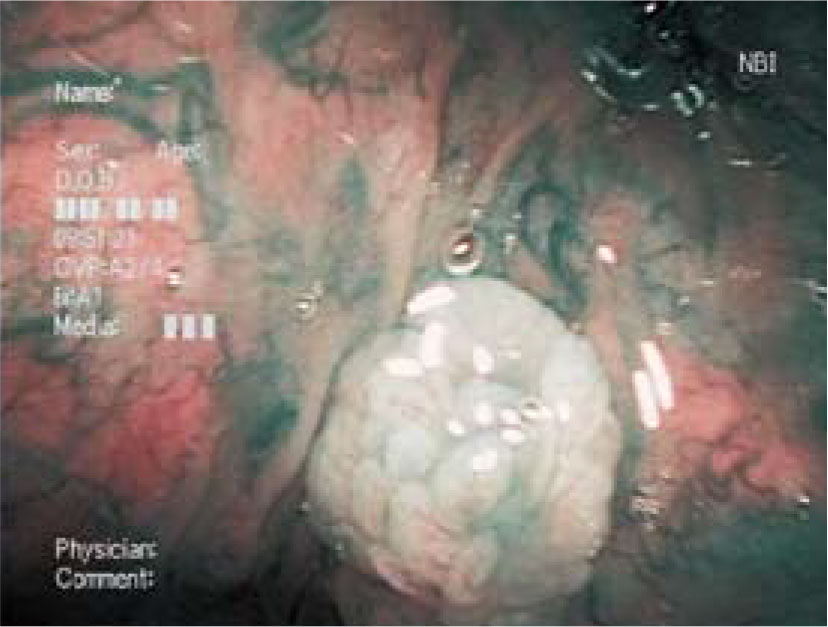

中咽頭乳頭腫(喉頭蓋谷左) 61 歳・男性 通常光 NBI 病 理 コメント: 通常光観察にて喉頭蓋谷左に白色病変が認められる。NBI 近接観察にて白色の腫瘤は分葉状で、その中に細く均一な毛細血管が認められ、乳頭腫が疑われた。生検の病理診断は乳頭腫であった。 上咽頭癌(軟口蓋上面)の表在癌 下咽頭リンパ濾胞(左梨状陥凹)